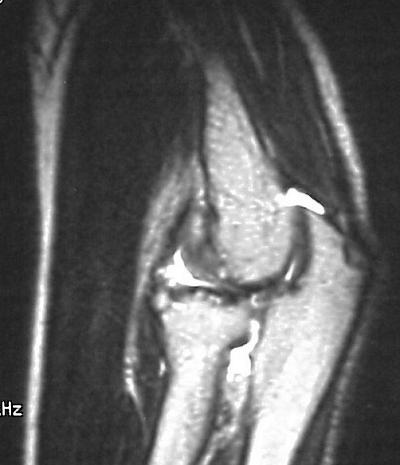

MRI shows an osteochondral sequestrum of the anterior capitellum:

Click for larger image